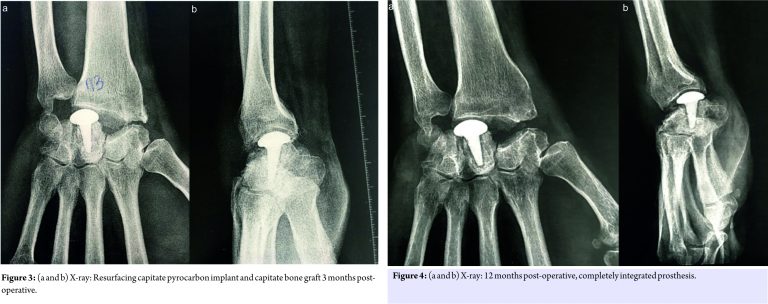

A 55-year-old left-handed man complained of right wrist pain over 5 years. There was no history of systemic illness, steroid abuse, inflammatory disease, or specific trauma. He already had surgery for his SNAC III left wrist: RCPI resurfacing. He also had a history of bilateral carpal tunnel surgery and used to work as a drywall guy. Physical examination: Right wrist: Extension 5°, flexion 10°; left wrist: 20° extension, flexion 20°; no pronation restriction was found in either side. CTA and X-ray showed evolve SNAC III and a completely intramedullary bone resorption of the capitate, as an empty recipient, and a major dorsal synovitis (Fig. 1 and 2).

On the basis of this diagnosis and due to refractory severe pain that did not respond to conservative treatment, we discussed three therapeutic options: PRC with RCPI in case of a possible large bone graft intraoperatively, a pyrocarbon intermediate prosthesis like adaptative proximal scaphoid implant which is interposed between the radius and the second carpal row [7], or a complete arthrodesis of the wrist. We decided to perform an RCPI and bone graft. During surgery, we performed the PRC without any particular difficulty. The cortical bone of the capitate was good quality, and after ablation of endomedullary fibrosis we proceeded to the capitate bone graft with bone chips of 2–3 mm from the lunate and scaphoid, then we were able to implant the RCPI. The prosthesis was stable in all wrist movements. We had an uncomplicated post-operative course, and the patient was subsequently immobilized with a wrist cast for 4 weeks. After 3 months of follow-up, the physical examination in the right wrist showed the following: Flexion 20° and extension 20°, and it was pronation- and supination-free. The patient presented no pain and was satisfied with the operation. The X-ray shows a stable prosthesis (Fig. 3). The 1-year follow-up X-ray (Fig. 4) shows a completely integrated prosthesis.